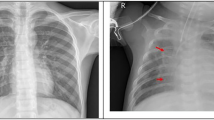

A dataset for pneumonia detection, RSNA13, was adopted as the training and testing dataset for this paper, which was published on the Kaggle platform. In this dataset, there are three different detection classifications, namely normal lung, lung without pneumonia but abnormal lung, and lung images with pneumonia. In total, 6012 different patients had at least one or more pneumonia conditions, which are collected by 18 radiologists from 16 different institutions. The mean value of labeler demographics’ experience is 10.6 years. The basic imaging examples of normal and pneumonia are shown in Fig. 3.